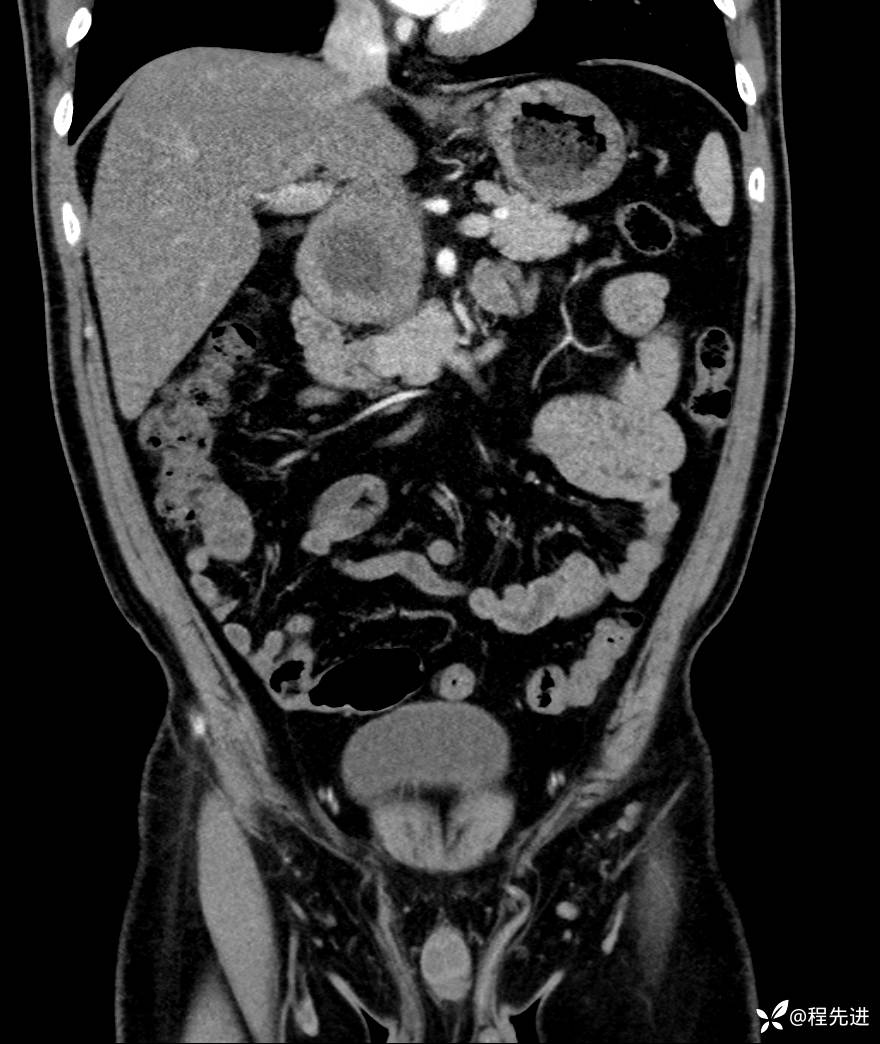

【腹盆】特别精彩病例|发现腹膜后肿物1月余

主诉:发现腹膜后肿物1月余

现病史:患者1月余前查体,行超声检查提示:后腹膜囊实性肿块;慢性胆囊炎伴胆囊内结石;无腹痛腹胀,不伴腹泻发热等;偶感腰背部酸痛。

CT平扫+增强: